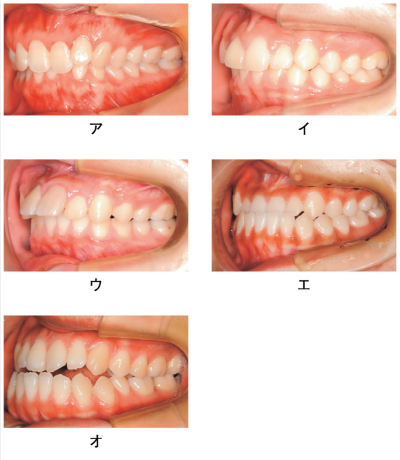

咬頭嵌合位の口腔内写真を別に示す。Angle Ⅱ級2類不正咬合はどれか。1つ選べ。

a. ア

b. イ

c. ウ

d. エ

e. オ